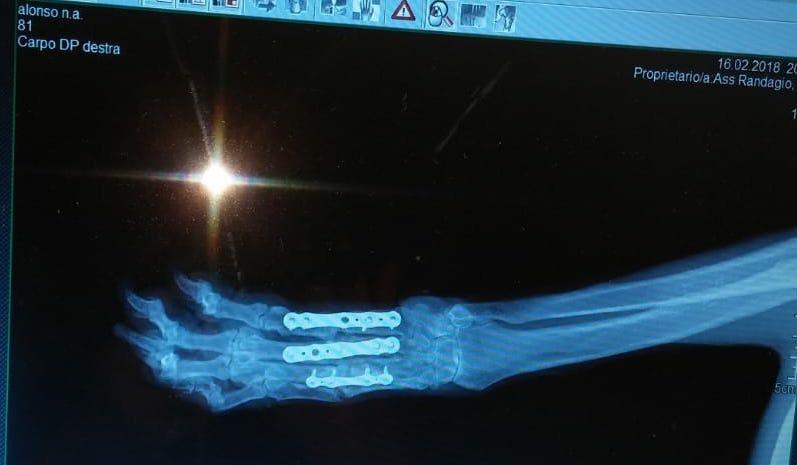

Zitat von Redaktion neu am 28. März 2021, 11:17 UhrAlonsos Lage schien aussichtslos zu sein. Im Dezember 2015 hatte ihn jemand überfahren, dabei brach er sich die rechte Vorderpfote. Statt operiert zu werden, wurde er ins Canile gebracht und dort ist die Pfote so zusammengewachsen, dass er sie nicht benutzen konnte. Im September 2017 haben ihn Tierschützer im Canile entdeckt und sofort rausgeholt. Alonso wurde dem Tierarzt vorgestellt und operiert. Nach einigen Monaten der Rehabilitation kann Alonso jetzt wieder richtig laufen. Er lebt nun in einem von einem befreundeten Tierschutzverein betriebenen Tierheim in Mailand und wartet auf seine Chance auf ein neues Leben.

Alonsos Lage schien aussichtslos zu sein. Im Dezember 2015 hatte ihn jemand überfahren, dabei brach er sich die rechte Vorderpfote. Statt operiert zu werden, wurde er ins Canile gebracht und dort ist die Pfote so zusammengewachsen, dass er sie nicht benutzen konnte. Im September 2017 haben ihn Tierschützer im Canile entdeckt und sofort rausgeholt. Alonso wurde dem Tierarzt vorgestellt und operiert. Nach einigen Monaten der Rehabilitation kann Alonso jetzt wieder richtig laufen. Er lebt nun in einem von einem befreundeten Tierschutzverein betriebenen Tierheim in Mailand und wartet auf seine Chance auf ein neues Leben.